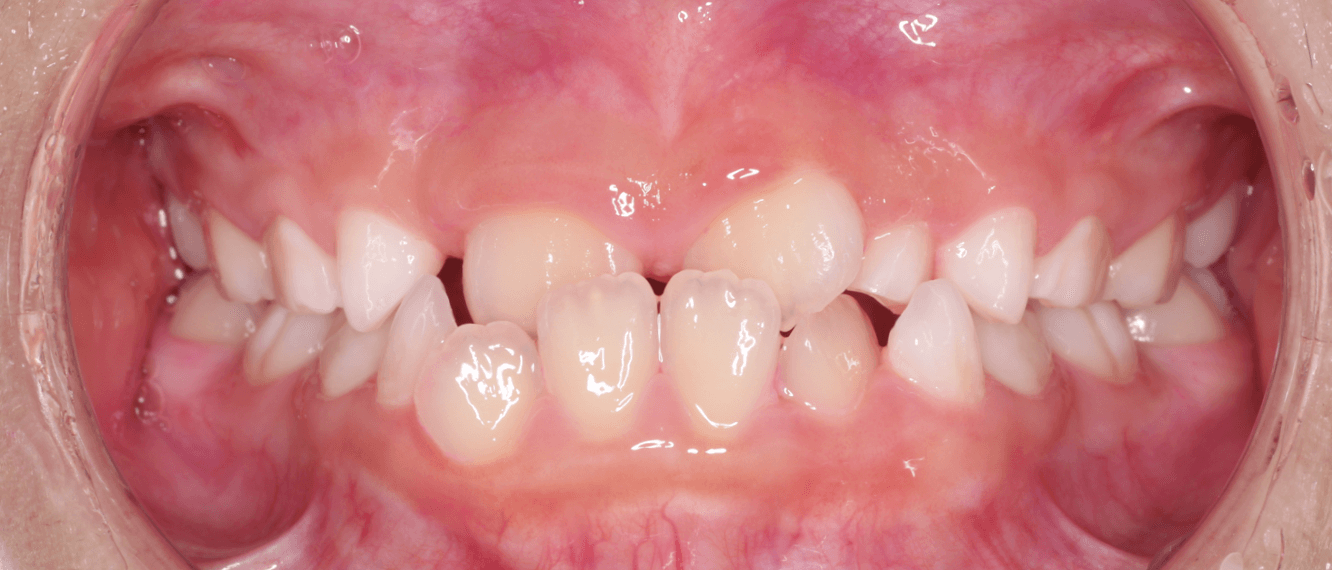

下の前歯のがたつきの様子

下の前歯の歯並びが前後的に乱れているだけなら、マウスピース装置で内側に傾けることで改善できますが、下の前歯にねじれや傾きの問題がある場合は、スペース不足が大きく、内側への移動が難しくなるため難易度が高まります。

そうすると、下の前歯にすき間がある受け口の方が治療は有利となります。